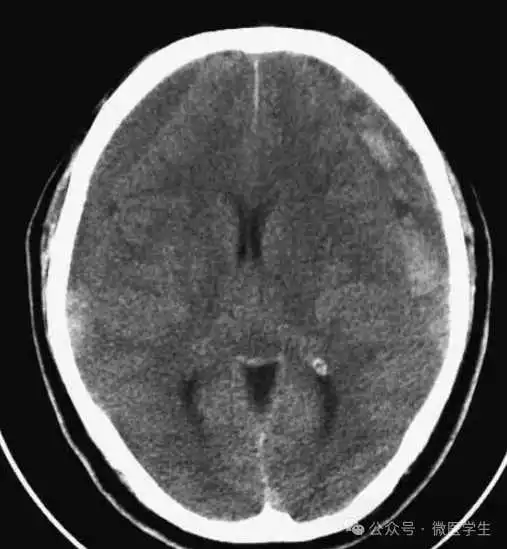

▲

动脉瘤破裂导致蛛网膜下腔出血、

脑室积血、非交通性脑积水。

与外伤性蛛网膜下腔出血不同,动脉瘤破裂导致的SAH常不累及大脑凸面,而位于基底池附近。脑动脉瘤常位于鞍上池的Willis环血管。

A:四脑室积血;

B:中脑导水管、环池、右侧侧脑室颞角积血,前交通动脉处(动脉瘤好发位置)出血密度较高;

C:三脑室积血;

D-F:侧脑室积血,蛛网膜下腔出血(血液代替了脑脊液)。